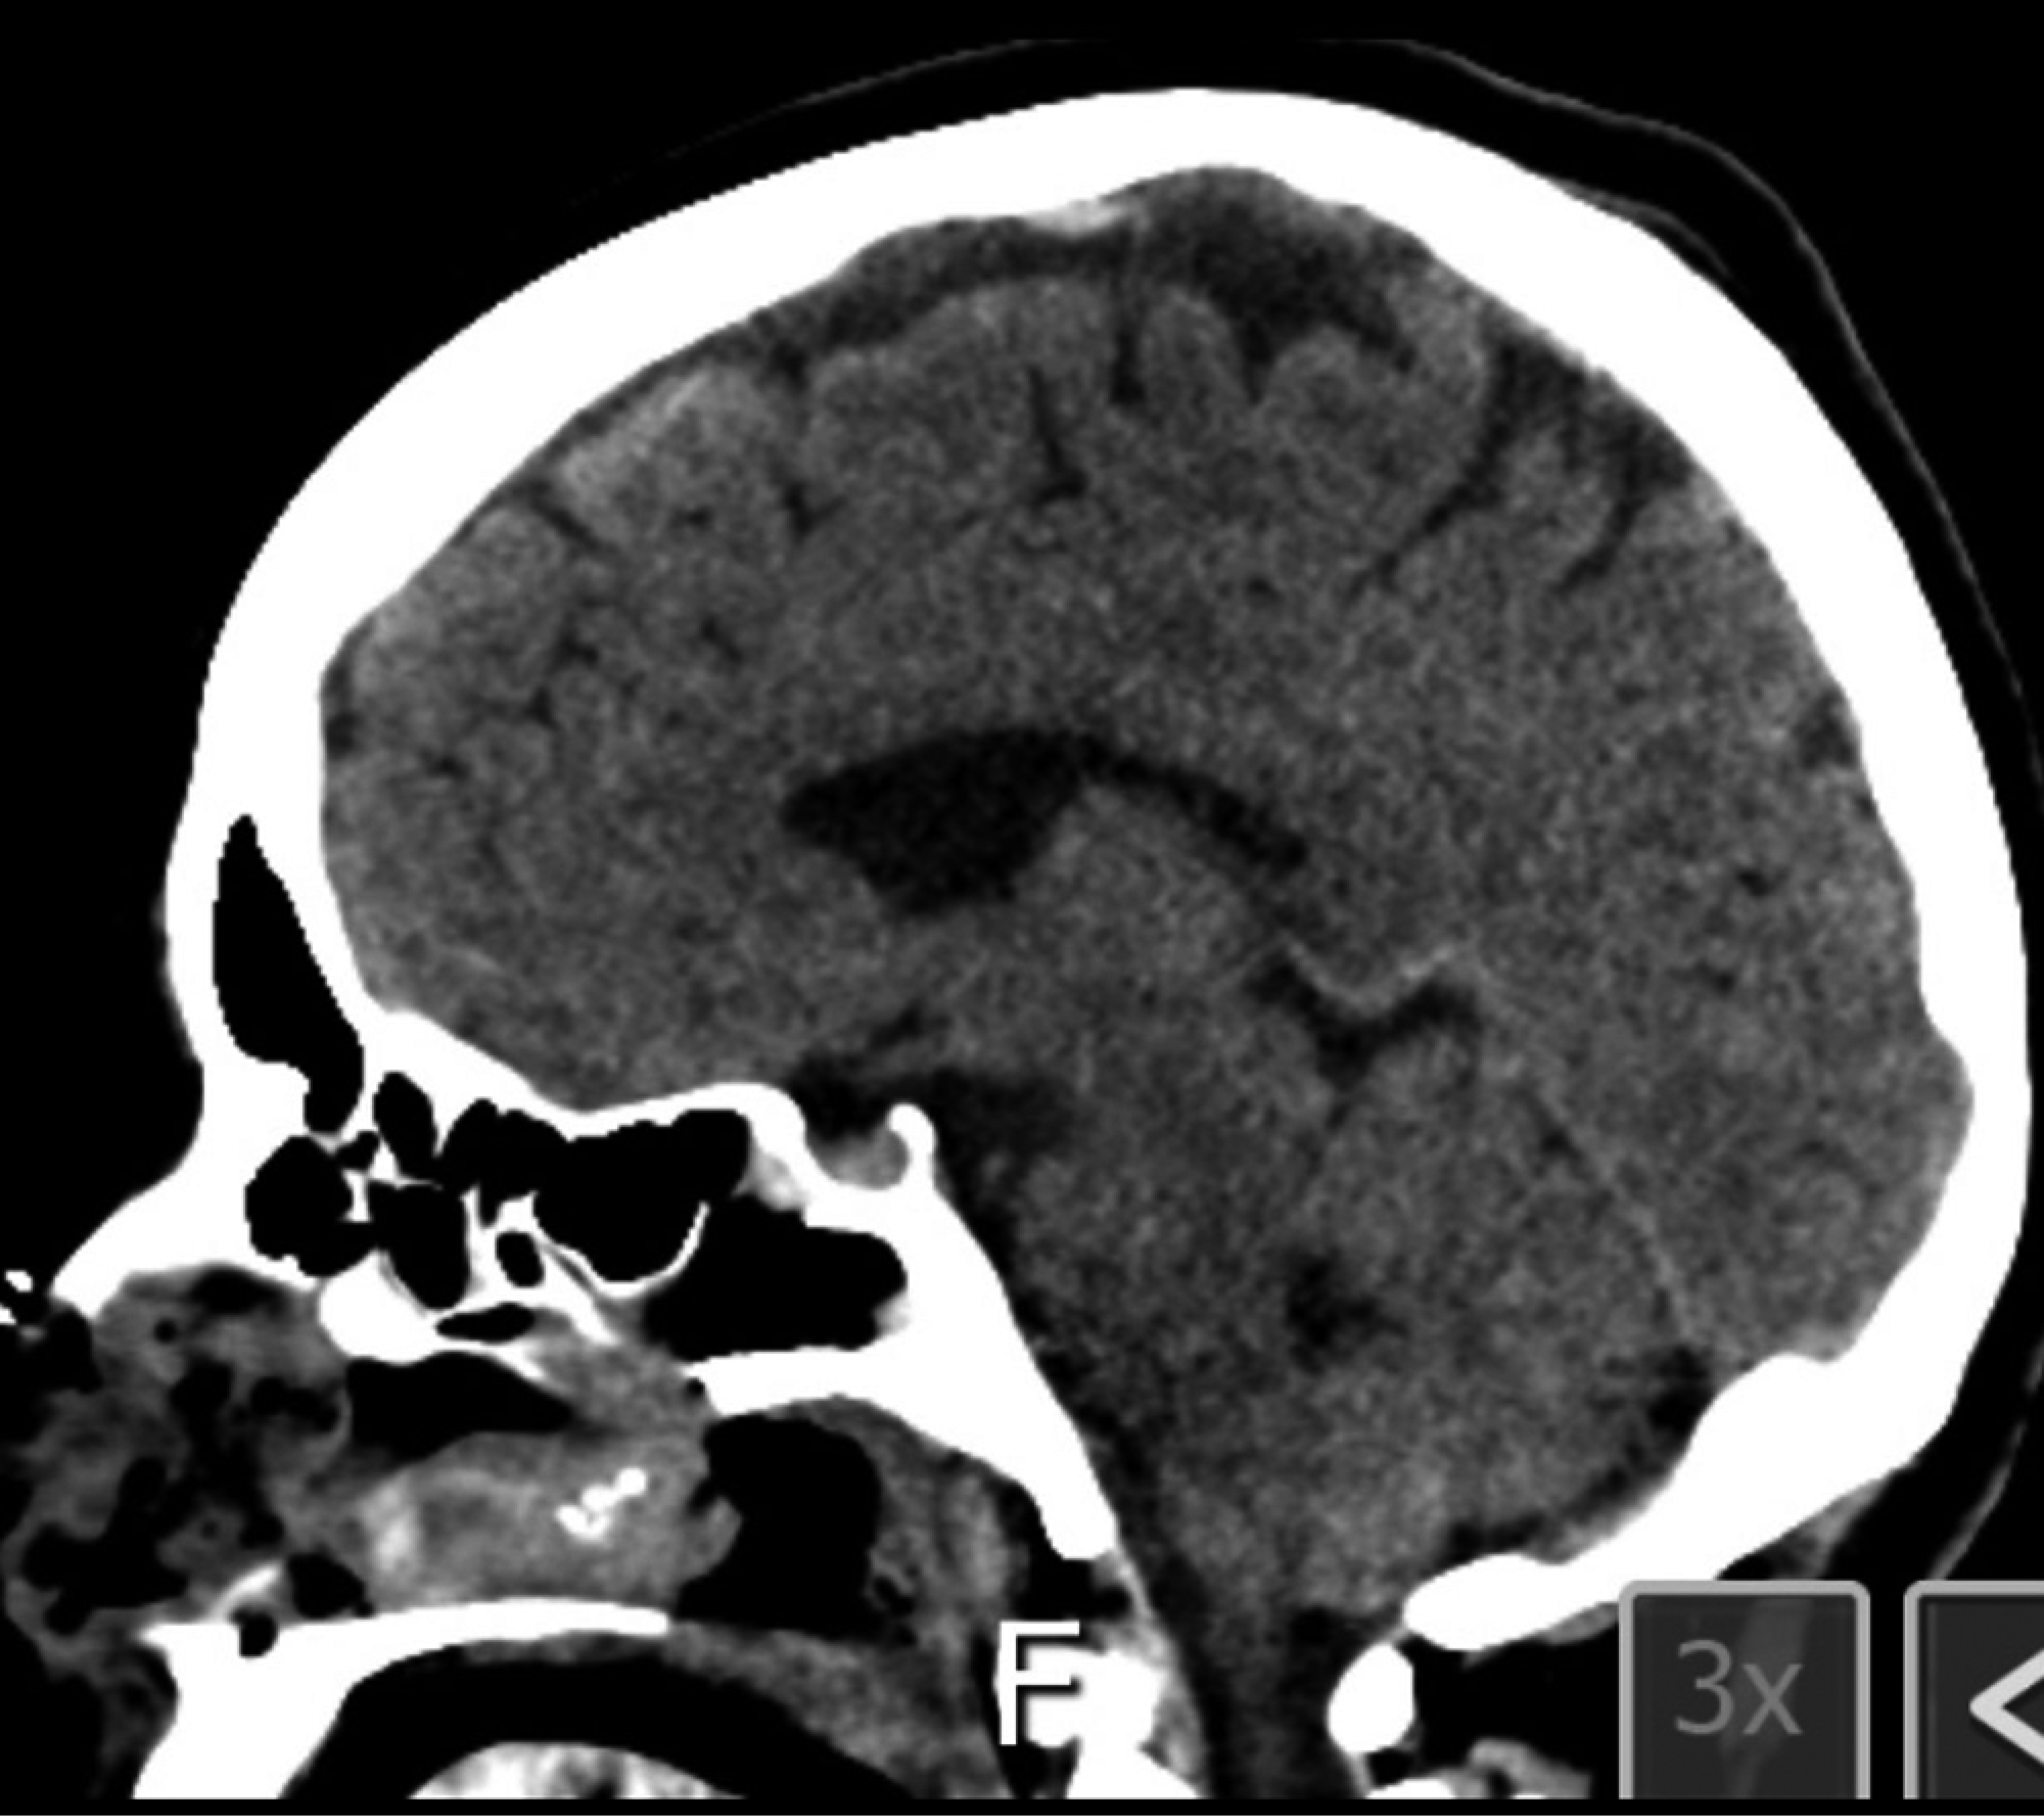

Se trata de mujer de 45 años que inició padecimiento en el 2018 con presencia de cefalea, fue tratada con analgésicos y hemianopsia bitemporal de predominio izquierdo, por lo que acudió a realizarse tomografía axial computarizada (TAC) simple y contrastada de cráneo, en donde se identificó lesión selar. Continuó con protocolo diagnóstico con imagen por resonancia magnética (IRM) de cráneo y se encontró lesión selar (Figura 5). Se inició protocolo preoperatorio solicitando los siguientes estudios: campimetría visual computarizada con hemianopsia bitemporal, perfil hormonal sin alteraciones, laboratorio paraclínico normal, radiografía de tórax, electrocardiograma normal y valoración preoperatoria por parte de los servicios de medicina interna y endocrinología para recibir recomendaciones sin contraindicación.

Diagnóstico por imágenes. La placa simple de cráneo en perfil estricto muestra en 80% de las lesiones sintomáticas abombamiento y erosión de la silla turca.6 En la TAC de cráneo estos quistes son en general hipodensos. En algunas ocasiones con realce al contraste en forma de anillo, en especial cuando presentan focos de epitelio escamoso.1-4,9 La IRM de cráneo muestra la extensión supraselar de estas lesiones, la relación con los nervios ópticos, quiasma e hipotálamo.1,9,10

Figura 5